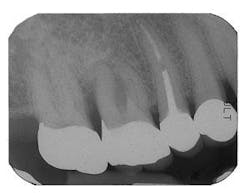

Figure 7 - Extraction Tooth No. 3 / Perioglas graft

Figure 8 - Healed bone graft Tooth No. 3

If an extraction is contemplated in an area that will involve future tooth replacement, it is important to consider bone preservation and regeneration at the extraction site. This is necessary to create sufficient bone for a future dental implant, or to preserve esthetics of the ridge if a fixed bridge will be considered. The regenerative capacity of the body is optimal at the time of extraction, so if the site may be thoroughly debrided without concern of leaving residual infection, it is generally best to graft at the time of extraction. The technique involves atraumatically removing the tooth, using a periotome if necessary to preserve as much socket bone as possible. In endodontically treated molars, it is frequently advisable to section the tooth first, so that roots may be removed without trauma and loss of bone. The socket is debrided carefully, removing all tissue tags; a large round bur is used in the socket as an aid in this process. Intramarrow penetration is established and a mixture of Bioglass® material (prepared as previously described) is gently layered into the defect, confirming the presence of blood. Collagen or a connective tissue graft is placed over the graft and the area closed if primary closure is not possible. The area may be protected by a periodontal dressing (if stability may be achieved) or a temporary removable treatment partial (“flipper”). It is important to avoid trauma and pressure over the graft site for several weeks. The site is monitored with a post-bone graft radiograph and again at six to eight months to evaluate the site for a dental implant if that is the intended treatment plan. In most cases, a CT scan is then obtained in order to obtain three-dimensional information on the quantity and quality of bone prior to implant placement.